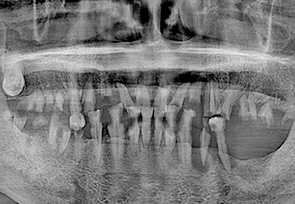

before

after